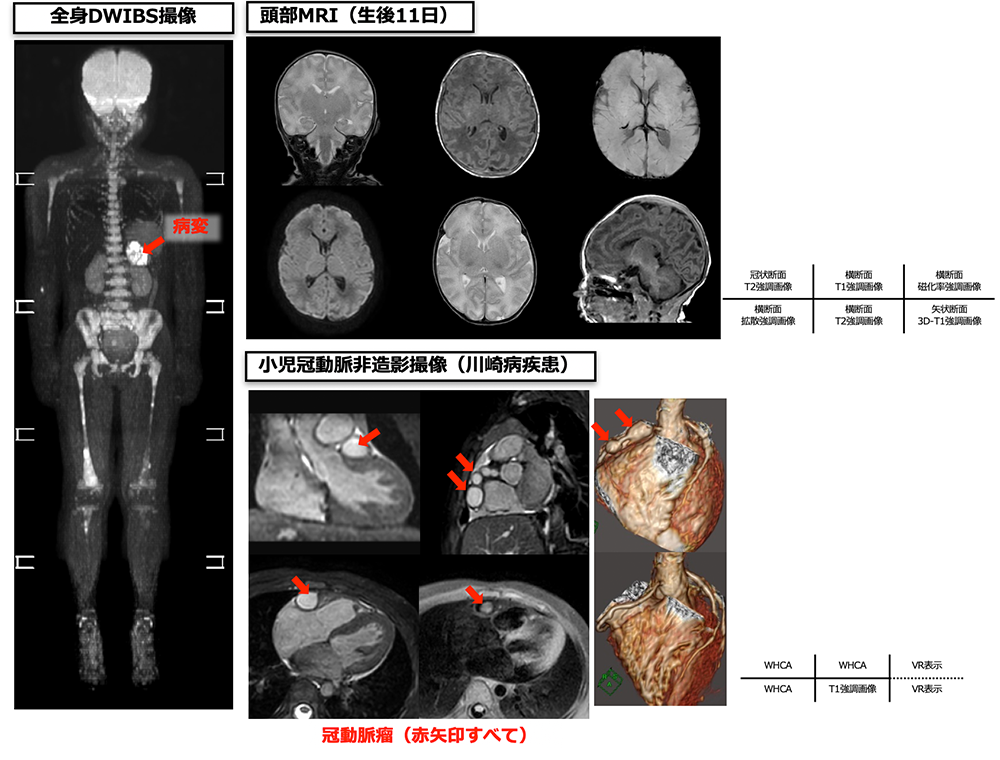

主に頭部や腹部の検査を行っており、生後まもない新生児から撮像することができます。特殊な検査としては、冠動脈撮像や全身DWIBS撮像があります。冠動脈撮像は、川崎病患者に対し造影剤を使用せずに冠動脈瘤の評価を行うことができます。全身DWIBS撮像は造影剤を使用することなく、全身の腫瘍の検索や治療効果の判定を行うことができます。